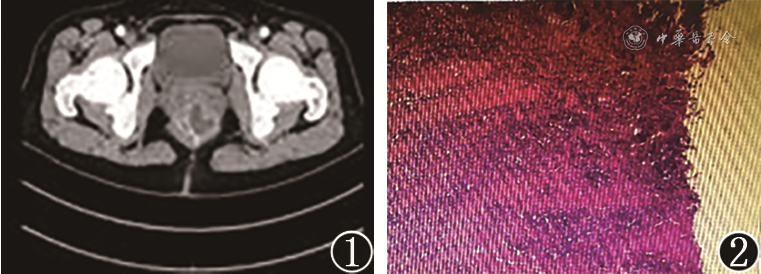

患者女,59岁,因“排便时肛周疼痛7 d”就诊。直肠指诊:距肛缘约5 cm至肛缘直肠后壁可触及肿物,大小约4.5 cm×4.0 cm,触之较软,黏膜光滑,活动度尚可。腹部CT检查示:直肠下段肠壁不均匀增厚,最厚处约4.4 cm,增厚肠壁内见斑片状低密度影,增强扫描明显不均匀强化,相应节段肠腔变窄,与周围组织关系尚可(图1)。肠镜检查见直肠距肛缘约5 cm至肛缘广基扁平隆起,大小约5 cm×4 cm,表面尚光滑,黏膜未侵及。初步诊断:骶前囊肿。行经肛门骶前囊肿切除术,于隆起处切开直肠全层直达骶前见囊性肿物,沿肿物囊壁将肿物完整切除,确定无残留后用可吸收线间断缝合直肠全层。病理检查示:(骶骨前肿物)符合尾肠囊肿,囊壁内衬鳞状上皮及立方上皮,局部伴慢性炎症,可见泡沫细胞(图2)。